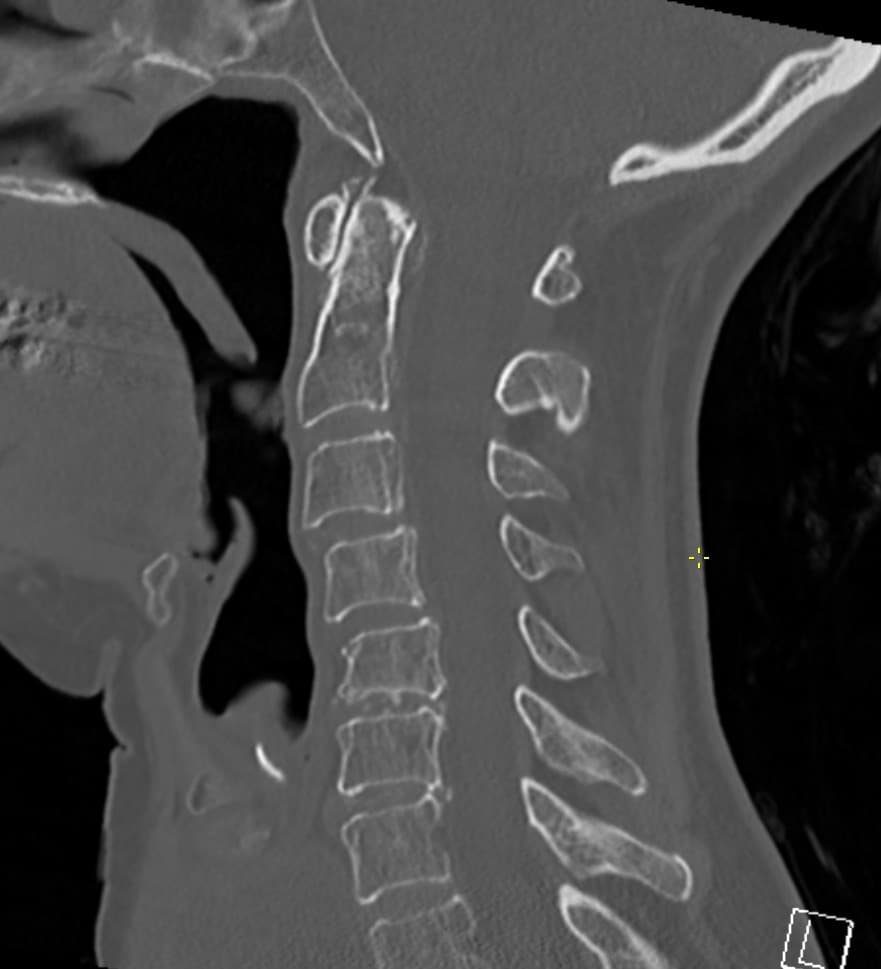

في إصابات العظام المعقدة، قد تؤثر الشقوق القشرية الدقيقة أو عدم تطابق الأسطح المفصلية أو تقليل تقدير الإزاحة بشكل مباشر على خطة العلاج.

الرأي الثاني المتخصص في CT يجب أن يغطي نمط الكسر، ومشاركة السطح المفصلي، وتأثير المحاذاة، والجوانب ما بعد الجراحة عند الحاجة.